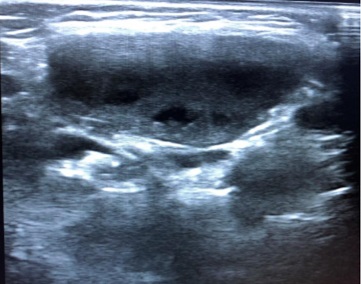

Niño de 3 años que acude por adenopatía cervical grande no dolorosa de semanas de evolución. Asintomático. Recibe tratamiento con amoxicilina-clavulánico durante dos semanas sin mejoría. En la exploración física: adenopatía de consistencia elástica, no móvil y no dolorosa. Se realiza ecografía objetivando adenopatía heterogénea con focos hipoecoicos (necrosis) con bordes irregulares, forma ovalada (Fig. 4) sin visualizar imagen Doppler central (Fig. 5), con artefactos en zonas periféricas. Se realiza Mantoux positivo y se deriva para estudio y exéresis quirúrgica diagnóstica y terapéutica. Se aísla Mycobacterium avium y recibe tratamiento con rifampicina.

Figura 4. Adenopatía heterogénea con focos hipoecoicos